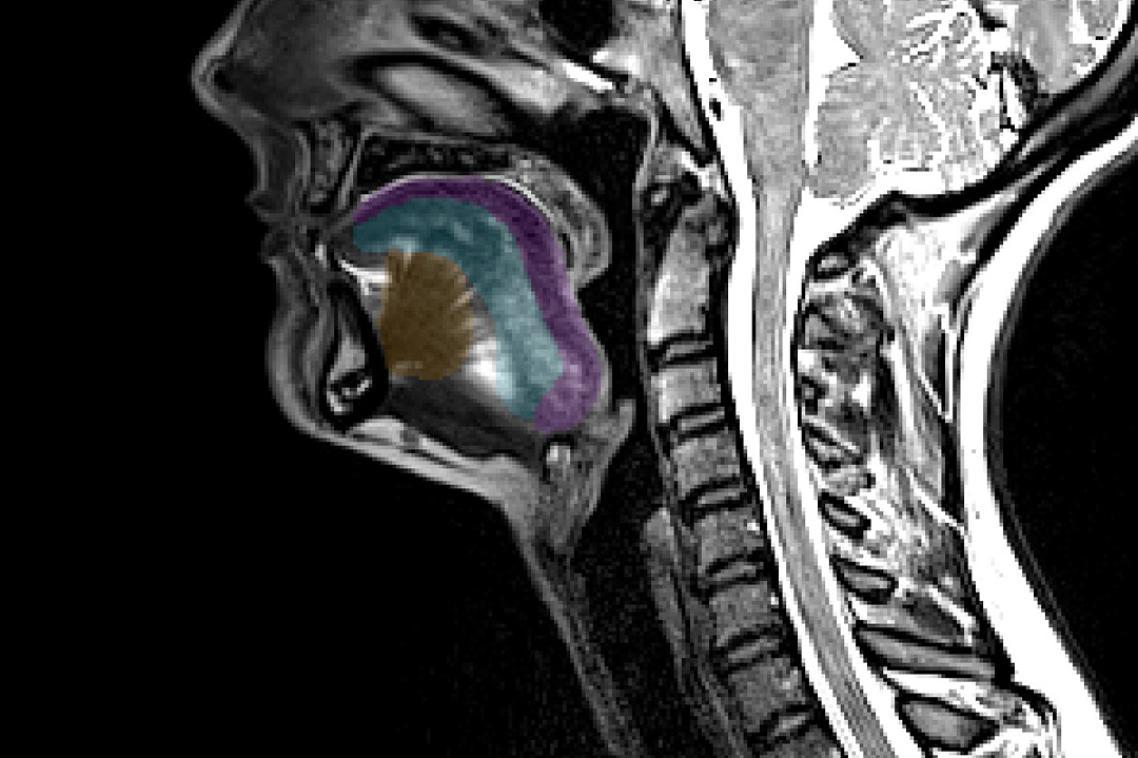

La maladie de Charcot pourrait être repérée précocement grâce à la langue. Des chercheurs de l’université du Queensland en Australie le démontrent dans une étude parue dans Computers in Biology and Medicine. Ils ont découvert qu’un examen de la langue par IRM permet de déterminer le risque de développer la maladie.

Le neuroscientifique et son équipe ont eu recours à une méthode combinant IRM et intelligence artificielle (IA). Ils se sont appuyés sur plus de 200 IRM, réalisées précédemment, de personnes atteintes et non-atteintes par la pathologie. "Nous avons pu obtenir des mesures précises du volume et de la forme des muscles de la langue, indique-t-il. (…) Des comparaisons transversales ont montré des différences significatives entre les scanners des personnes atteintes de SLA et celles des personnes non atteintes." Lors de précédents travaux, d’autres scientifiques ont remarqué que les personnes dont les symptômes de SLA concernent les muscles de la bouche, de la langue, de la gorge et du cou ont une survie plus courte que celles dont les symptômes apparaissent dans les membres. "Nos propres résultats le confirment : les personnes dont le volume de la langue est plus faible ont un pronostic plus sombre", précise le spécialiste.